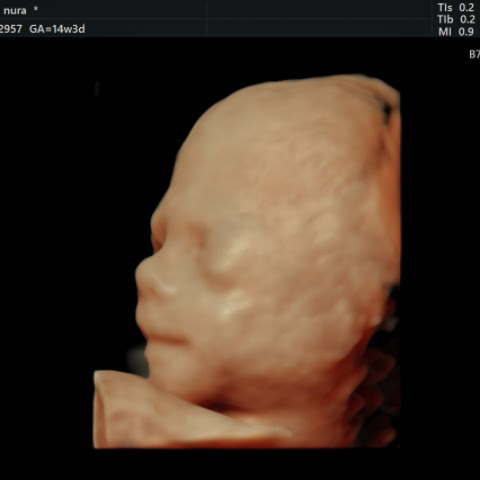

גלריה